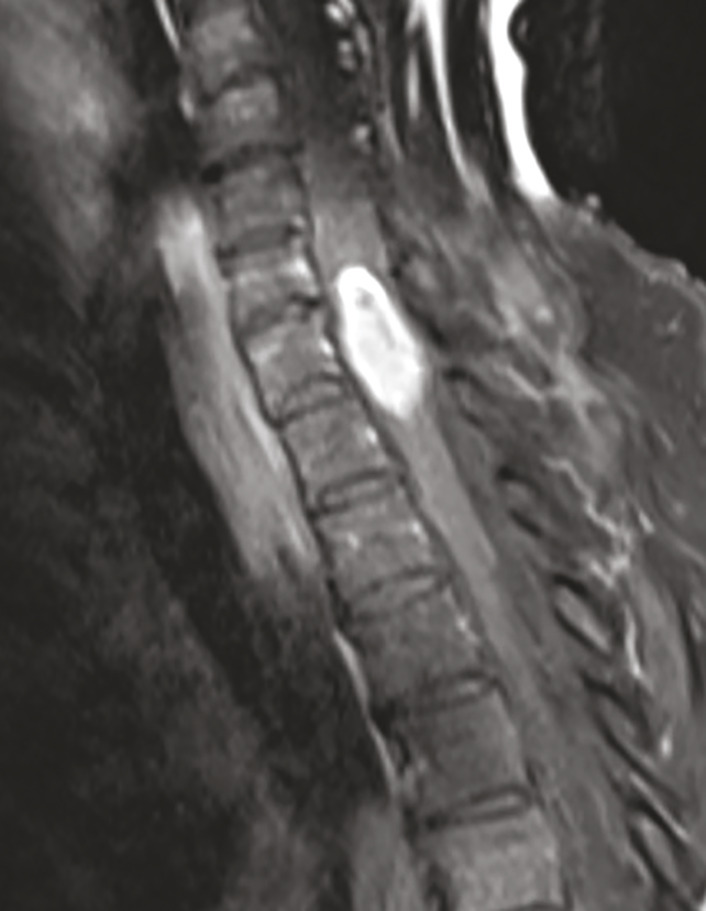

la coupe sagittale par IRM montre une masse fusiforme intramédullaire au niveau de C7.

Extrait de : Métastase intramédullaire d’un carcinome pulmonaire